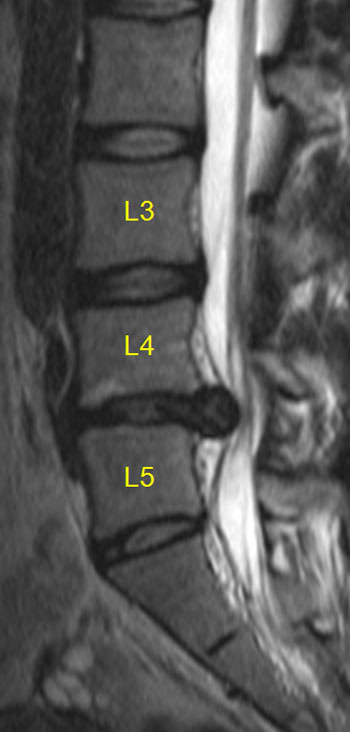

- ✅ MRIでヘルニアと断定され、この激痛は手術でしか取れないと言われた